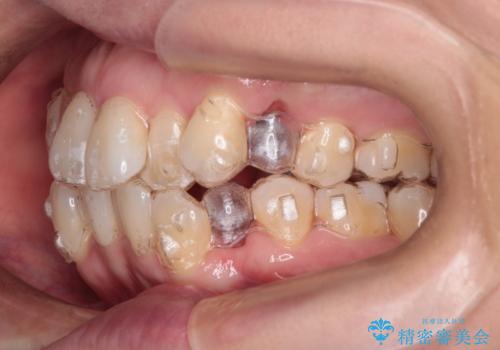

【抜歯ケース】前歯のガタガタをインビザラインで治療

- 前歯のガタガタを主訴に来院されました。

抜歯が必要なケースでしたが、インビザラインでの治療を希望されワイヤーを使用せずに治療を完了しております。

抜歯を伴う矯正治療はマウスピース矯正よりもワイヤー矯正の方がメリットが多いです。当院で抜歯を伴うマウスピース矯正を希望される場合は、場合によってワイヤーを使うことを了承していただいた上で治療を行なっています。